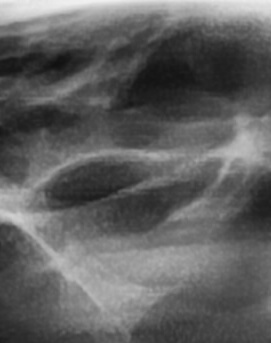

어금니 뒤 잇몸 부음 우선 원인부터 살펴보면 이러한 증상은 단순한 잇몸 염증에서부터 더 심각한 치주 질환이나 사랑니 문제까지 다양하게 발생할 수 있는데요. 보통 잇몸이 붓는 것은 세균 감염, 음식물 잔여물에 의한 자극, 치주 질환, 사랑니 문제 등이 원인이 되는 경우가 많으며 증상이 가벼울 때는 자연적으로 가라앉을 수도 있지만, 제대로 치료하지 않고 반복되는 잇몸 문제가 갈수록 진행된다면 염증이 심해지고 통증이 심해질 수 있고 잇몸이 주저 앉거나 심한 경우 치아가 흔들릴 수 있어서 원인을 정확하게 파악하고 적절한 치료를 받는 것이 중요하다고 볼 수 있어요

가장 주의해야 하는 문제 중에 치주염이 진행되면 어금니 뒤쪽뿐만 아니라 전체적인 잇몸이 약해질 수 있어요. 치주염은 치아를 둘러싸고 있는 조직이 손상되는 질환인데 특히 잇몸이 자주 붓거나 피가 나는 경우에는 치주염이 진행되고 있는 신호일 수 있기 때문에 단순한 잇몸 붓기로 넘기지 않는 것이 좋으며 치료를 받지 않으면 결국 치아를 지탱하는 뼈가 약해지고, 심한 경우에는 치아가 흔들리거나 빠질 수도 있었어요.

결론적으로는 통증이 심하거나 염증이 오래 지속되는 경우에는 치과를 방문해서 정확한 진단을 받는 것이 중요한데 단순한 잇몸 염증이라면 치석 제거와 항생제 치료로 호전될 수 있지만, 치주염이 진행된 경우라면 보다 적극적인 치료가 필요할 수 있어요. 만약 사랑니로 인해 잇몸이 자꾸 붓는다면 사랑니 발치를 고려해야 하겠고 사랑니가 완전히 매복되어 있다면 수술적인 방법으로 제거해야 할 수도 있어요. 특히 반복적으로 붓는다면 사랑니 검사를 받아보거나, 치과에서 정밀 검진을 통해 치주 상태를 확인하는 것이 필요하다는 점에서 어금니 근처의 잇몸이 반복적으로 불편하다면 꼭 치과를 찾아보시길 바라고 있어요